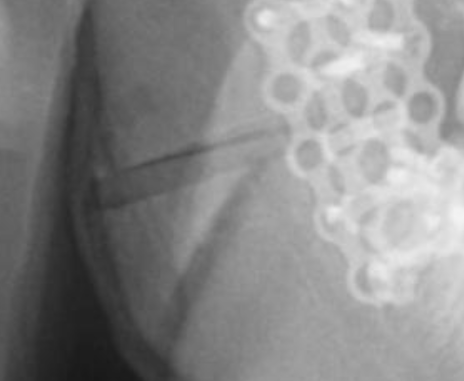

1770627749810

1770627816843

Bro you gotta be fucking kidding me @sayonara @Gargantuan nigga better sue his surgeon atp

You ascended judging from your X-rays. You just need to wait until your swelling fully goes away.